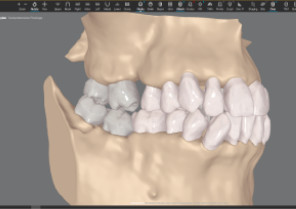

Auto-generates a 3D model with roots, crown, and bone for more-informed treatment planning.

See patients' roots, crowns, and bone in one auto-generated 3D model with new CBCT integration.

Shows you real root renderings and bone visualizations based on actual scan data.

Simulates root movement along with tooth movement.

Roots and gingiva

Roots only

Roots with semitransparent bone

Roots and bone